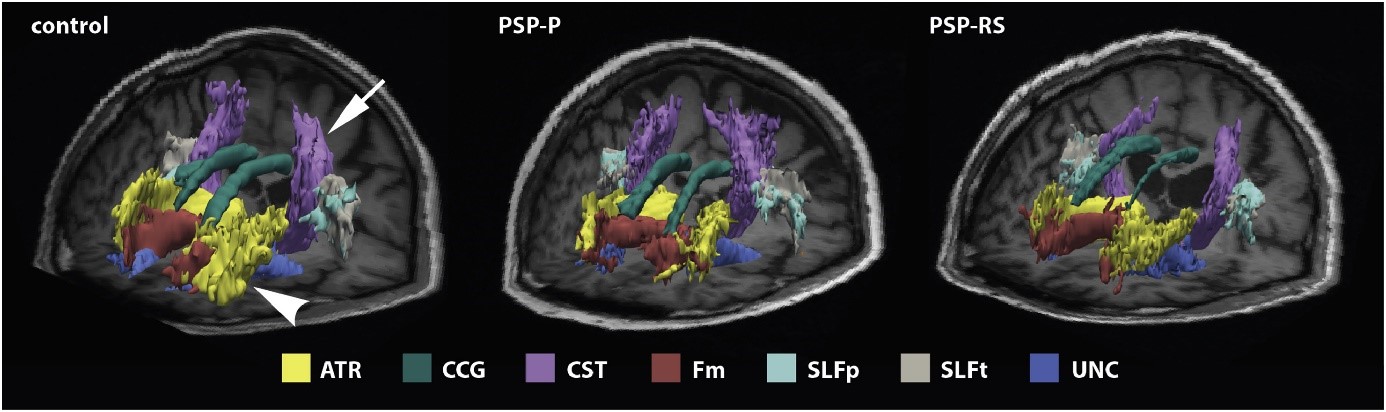

Fig. 1: Diagnostic potential of automated tractography in progressive supranuclear palsy (PSP) variants: Visualisation of white matter tracts as reconstructed by TRACULA and rendered on a 3D T1-weighted MRI of a healthy participant (left), a PSP-P (middle) and a PSP-RS (right) patient. Reprinted from the publication “Potrusil-T et al., Parkinsonism and Related Disorders 2020 Mar;72:65-71, doi: 10.1016/j.parkreldis.2020.02.007. (Fig. 1.) ”, with permission from Elsevier

Research Group Computational Neuroscience

- Krismer F, Seppi K, Göbel G, Steiger R, Zucal I, Boesch S, Gizewski ER, Wenning GK, Poewe W, Scherfler C: Morphometric MRI profiles of multiple systematrophy variants and implications for differential diagnosis. MOVEMENT DISORDERS: 2019; 34(7):1041-1048.